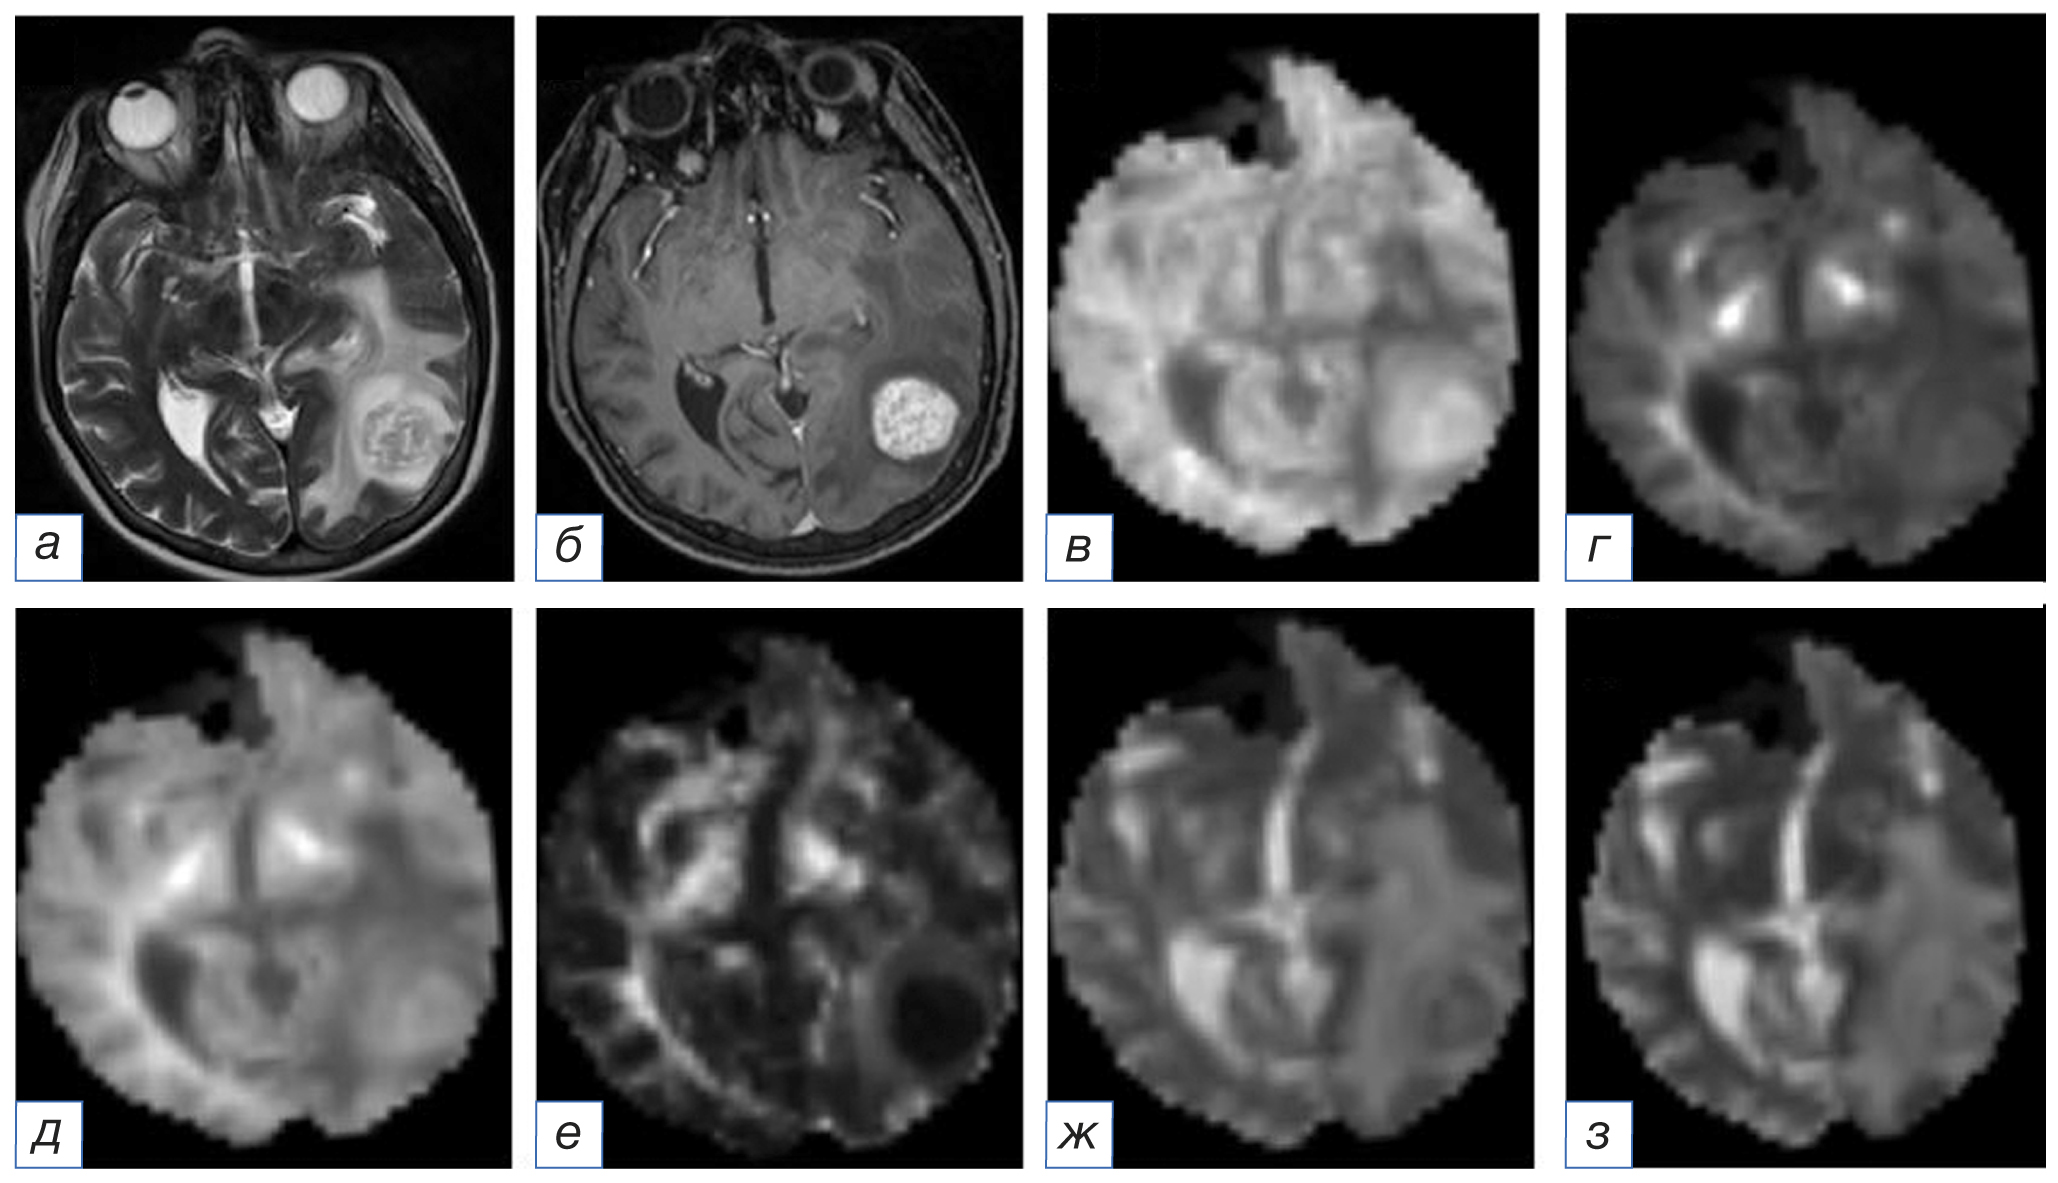

Рис. 5. Магнитно-резонансная томограмма головного мозга: метастаз меланомы в левой височно-затылочной области: а (T2-WI) — в левой височно-затылочной области определяется образование с кистозными включениями, окружённое выраженной зоной перифокального отёка; б (Т1-WI после внутривенного введения контрастного вещества) — визуализируется интенсивное неравномерное накопление контрастного препарата; в (аксиальный куртозис) — в левой височно-затылочной области образование определяется в виде участка преимущественно повышенного МР-сигнала; г (радиальный куртозис) — в левой височно-затылочной области образование определяется в виде участка слабо повышенного МР-сигнала; д (средний куртозис) — в левой височно-затылочной области образование определяется в виде участка преимущественно повышенного МР-сигнала; е (куртозисная анизотропия — в левой височно-затылочной области образование определяется в виде участка пониженного МР-сигнала; ж (аксиальная диффузия экстрааксональной жидкости) — в левой височно-затылочной области образование определяется в виде участка гетерогенного МР-сигнала; з (радиальная диффузия экстрааксональной жидкости) — в левой височно-затылочной области образование определяется в виде участка гетерогенного МР-сигнала.